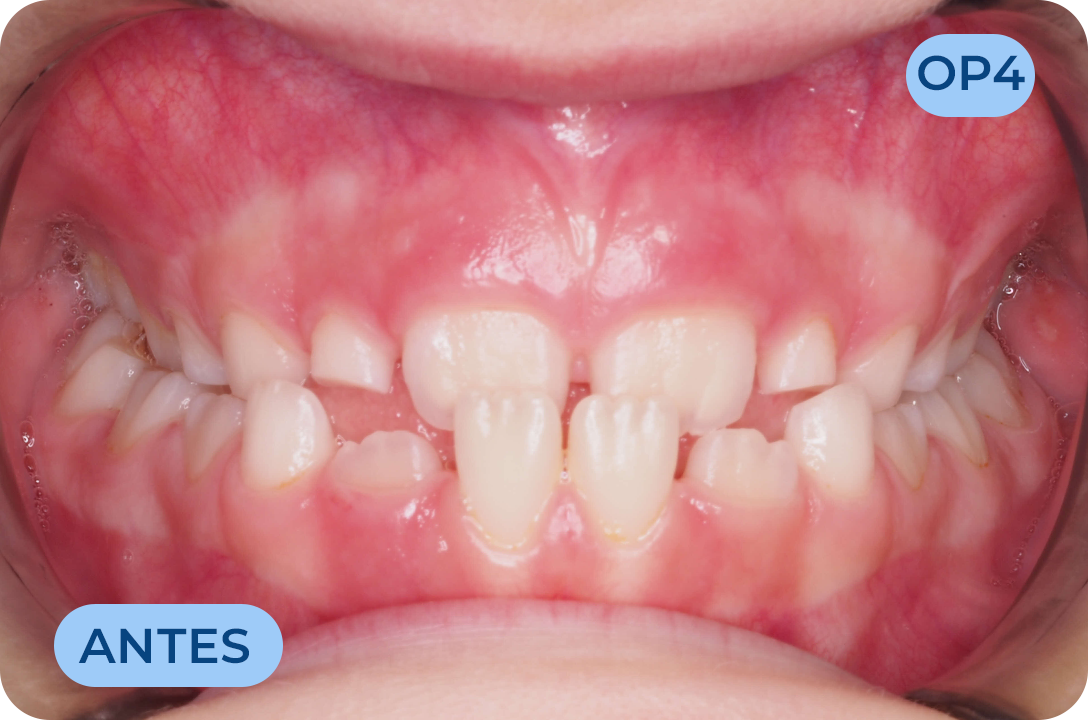

Ortodontia

É a especialidade da Medicina Dentária que se debruça sobre o estudo e correção das más posições dentárias e dos maxilares. Atualmente é possível tratar pacientes de todas as idades, no entanto a 1ª consulta deve ser realizada ainda na infância para intercetar eventuais problemas de desenvolvimento esquelético e funcional.